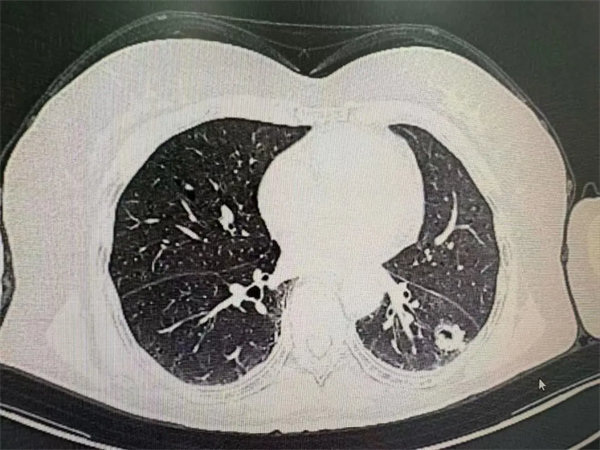

68岁的李女士因间断性上腹痛就医,经我院肝胆脾胰外一科检查,确诊为胆囊息肉,具备明确手术指征。然而,术前的胸部CT检查却意外发现其左肺下叶存在一枚直径约1.9cm的厚壁空洞,且壁厚薄不均、外后缘伴有小结节——这一异常信号,让诊疗团队立刻警惕起来。

“肺部结节若为恶性肿瘤,早期干预直接决定预后效果!”肝胆脾胰科副主任王锋第一时间组织团队讨论,并迅速联系胸外科启动多学科会诊。胸外科杨智主任团队仔细研判影像后,明确指出结节符合肺腺癌影像学特征,建议优先处理肺部病灶,为后续治疗定下关键方向。在与患者及家属充分沟通后,李女士迅速转入胸外科接受进一步诊疗。